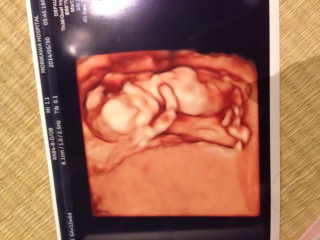

初めての妊娠♪(/ω\*)お腹の上から4Dエコーしてもらうとクネクネ動く姿が…♡残念ながら、後ろすがたしか見えなかったけど、腕や耳までちゃんとあるのが見れて感激♪

なんだかソファーで寛いでいるみたい☆ 今にも「ハロー!」と聞こえてきそう♪ こんなに小さいのに手の指まできちんと出来ていて、 感動しました☆

週数通りの大きさで順調だと言われ、ひと安心!頭を抱えているけど、なにか悩んでいるの?笑